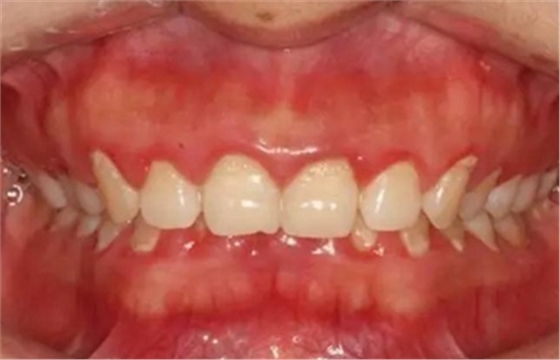

3、牙齦炎癥狀況

(1)檢查牙齦色澤、形態(tài)和質(zhì)地的變化,用文字描述。

(2)用指數(shù)記分法如牙齦指數(shù)(GI)、齦溝出血指數(shù)(SBI)等量化指標來記錄牙齦的炎癥程度。

(3)用探診后牙齦有無出血表示牙齦有無炎癥,用鈍頭牙周探針的尖端,置于齦緣下約1 mm,輕輕沿齦緣滑動后觀察片刻有無出血。若出血,則記錄為陽性。